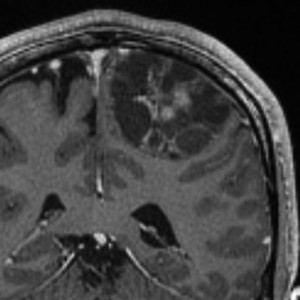

症候性てんかんで発症した30代の毛様粘液性星細胞腫です。術前診断で,のう胞性髄膜腫 cystic meningioma と間違えました。腫瘍内でごくわずかに出血していました。毛様細胞性星細胞腫は腫瘍内出血をしばしば生じます。実質部分はガドリニウム増強されていて多房性のう胞があります。成人型の毛様粘液性星細胞腫としては全く矛盾のない画像なのですが,発生した部位が頭頂葉皮質だったので術前診断できませんでした。eroquent areaなので完全摘出する必要はありません,のう胞壁を取り残しても再燃しません。